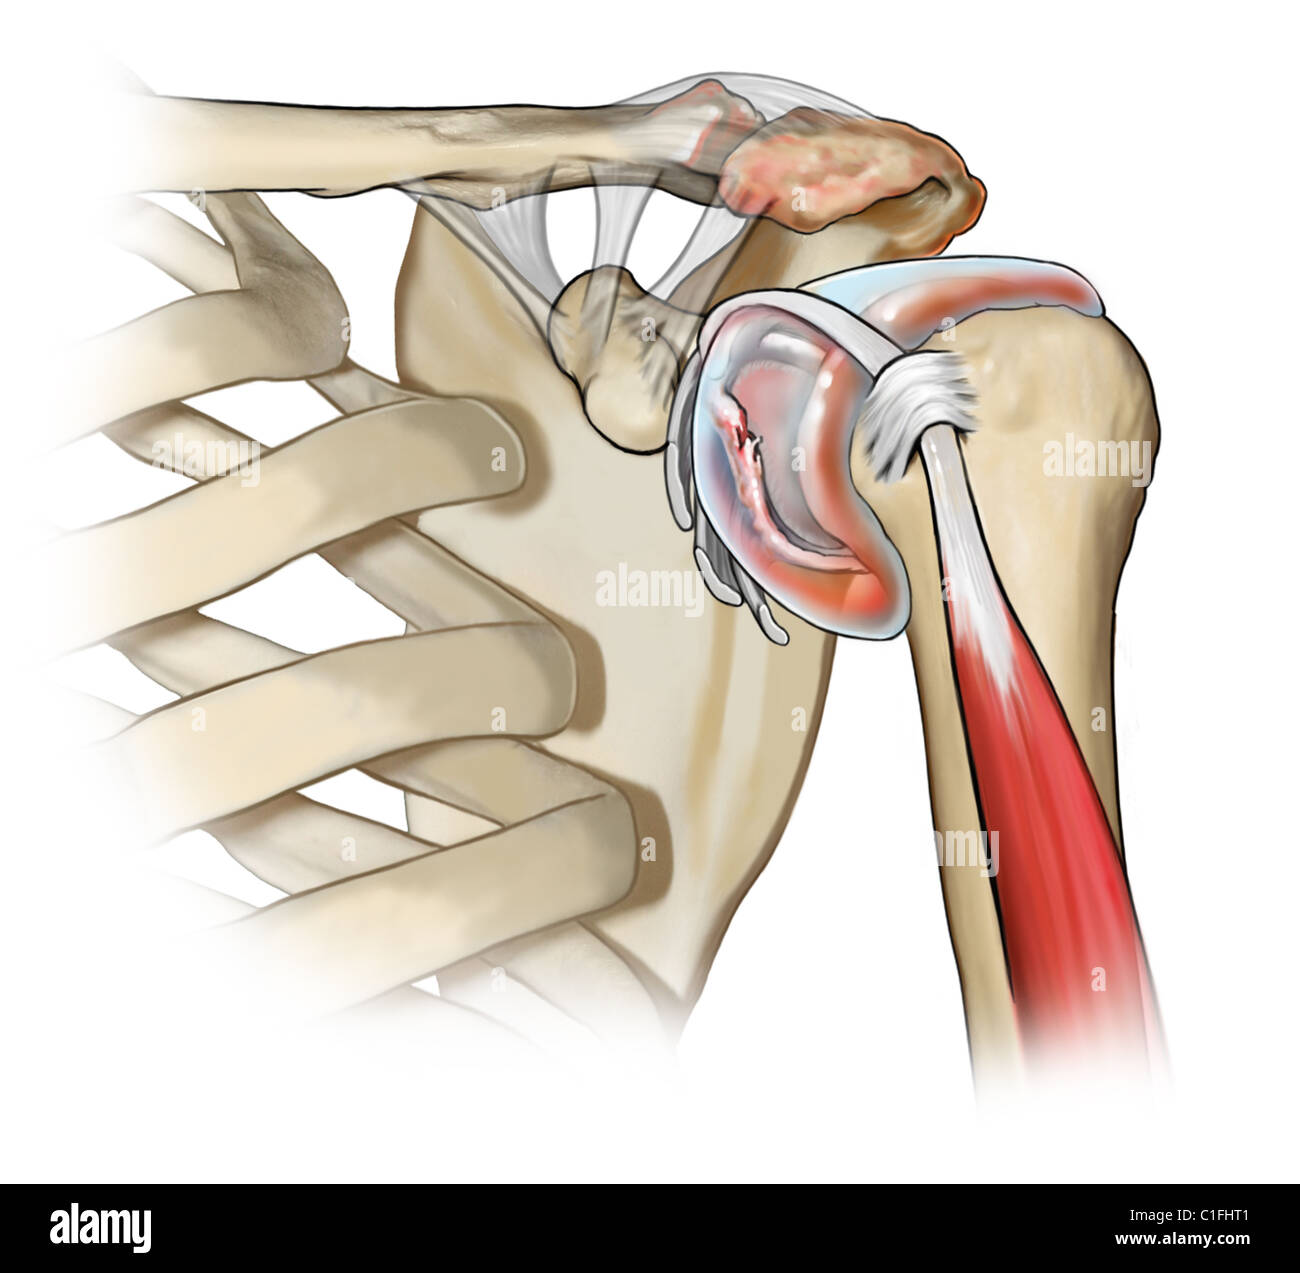

Фотографии мышц ротаторной манжеты плеча